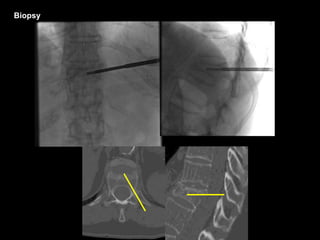

Biopsy